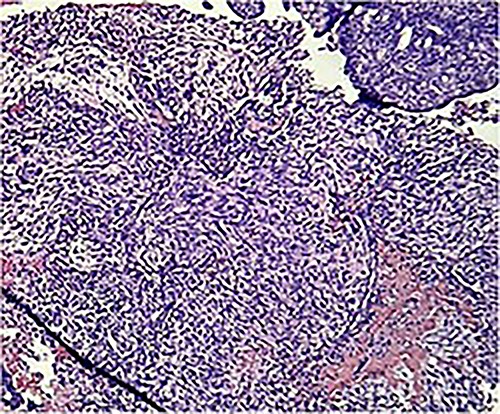

Macroscopically, an amorphous uterus weighing 397 g and measuring 12 × 9 × 7.5 cm with a brown serosa, and multinodular violaceous areas was examined. When incised, the endometrial cavity was occupied by a whitish polypoid mass of 8 × 5 cm which invaded the myometrium. In addition, multiple firm whitish nodules ~2 × 1.5 cm in diameter were identified. Bilateral ovaries and fallopian tubes appeared to be of normal morphology and size. Histologically, there was evidence of epithelial and sarcomatous components (Figs 1 and 2), and the epithelial component developed atypical glands (Fig. 3). The diagnosis of MMMT was given due to histologic findings.

Photomicrograph shows the presence of a malignant mixed tumor containing epithelial and sarcomatous components (H&E stain ×4).

Photomicrograph shows homologous sarcomatous components, composed of sarcomatous spindle shaped cells, with elongated nuclei and irregular nuclear membrane. (H&E stain ×10).